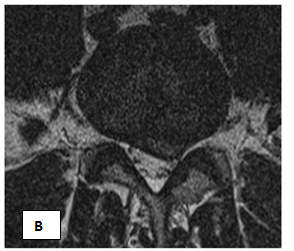

In February-March of 201 5 MFUVT course of 15 treatments was carried out. The conduct and course of UHT MF, pain decreased during the first 5 days, with th Lassega - 80 degrees, no lameness, pain on the VAS scale of 4 points. MRI (Figures 2A & 2B) Performed 2 months after the end of the UHT MF: Dorsal sided paramedian hernia L3/L4 disc, up to 0.5 cm, extending into the intervertebral foramen, on both sides, with their restrictions, as well as several caudal into the right lateral pocket, compressing the dural sac. Sequestration is not noted.

Figure 2 Sick F. Decrease in the size of herniated MTD after the course of UHT.